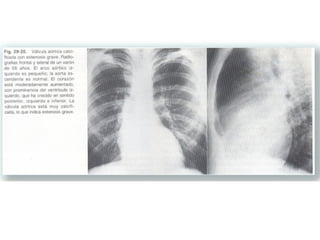

LA ESTENOSIS VALVULAR AÓRTICA  AISLADA PUEDE SER CONGÉNITA  O DEGENERATIVA, SEGÚN LA EDAD DEL PACIENTE. .PROVOCA UNA SOBRECARGA DE PRESIÓN QUE CONDUCE A UNA HIPERTROFIA VENTRICULAR IZQUIERDA. LA VÁLVULA ESTENÓTICA SUELE ESTAR CALCIFICADA

La  calcificación de la válvula aórtica está superpuesta a la columna en la proyección pa. por lo que no es visible. En la radiografía lateral puede verse a mitad de camino entre el borde cardiaco posterior y anterior. Si se traza una línea que, pasando por la bifurcación traqueal, llegue hasta el ángulo esternodiafragmático anterior, la válvula aórtica que­da por delante mientras que la válvula mitral queda por detrás.